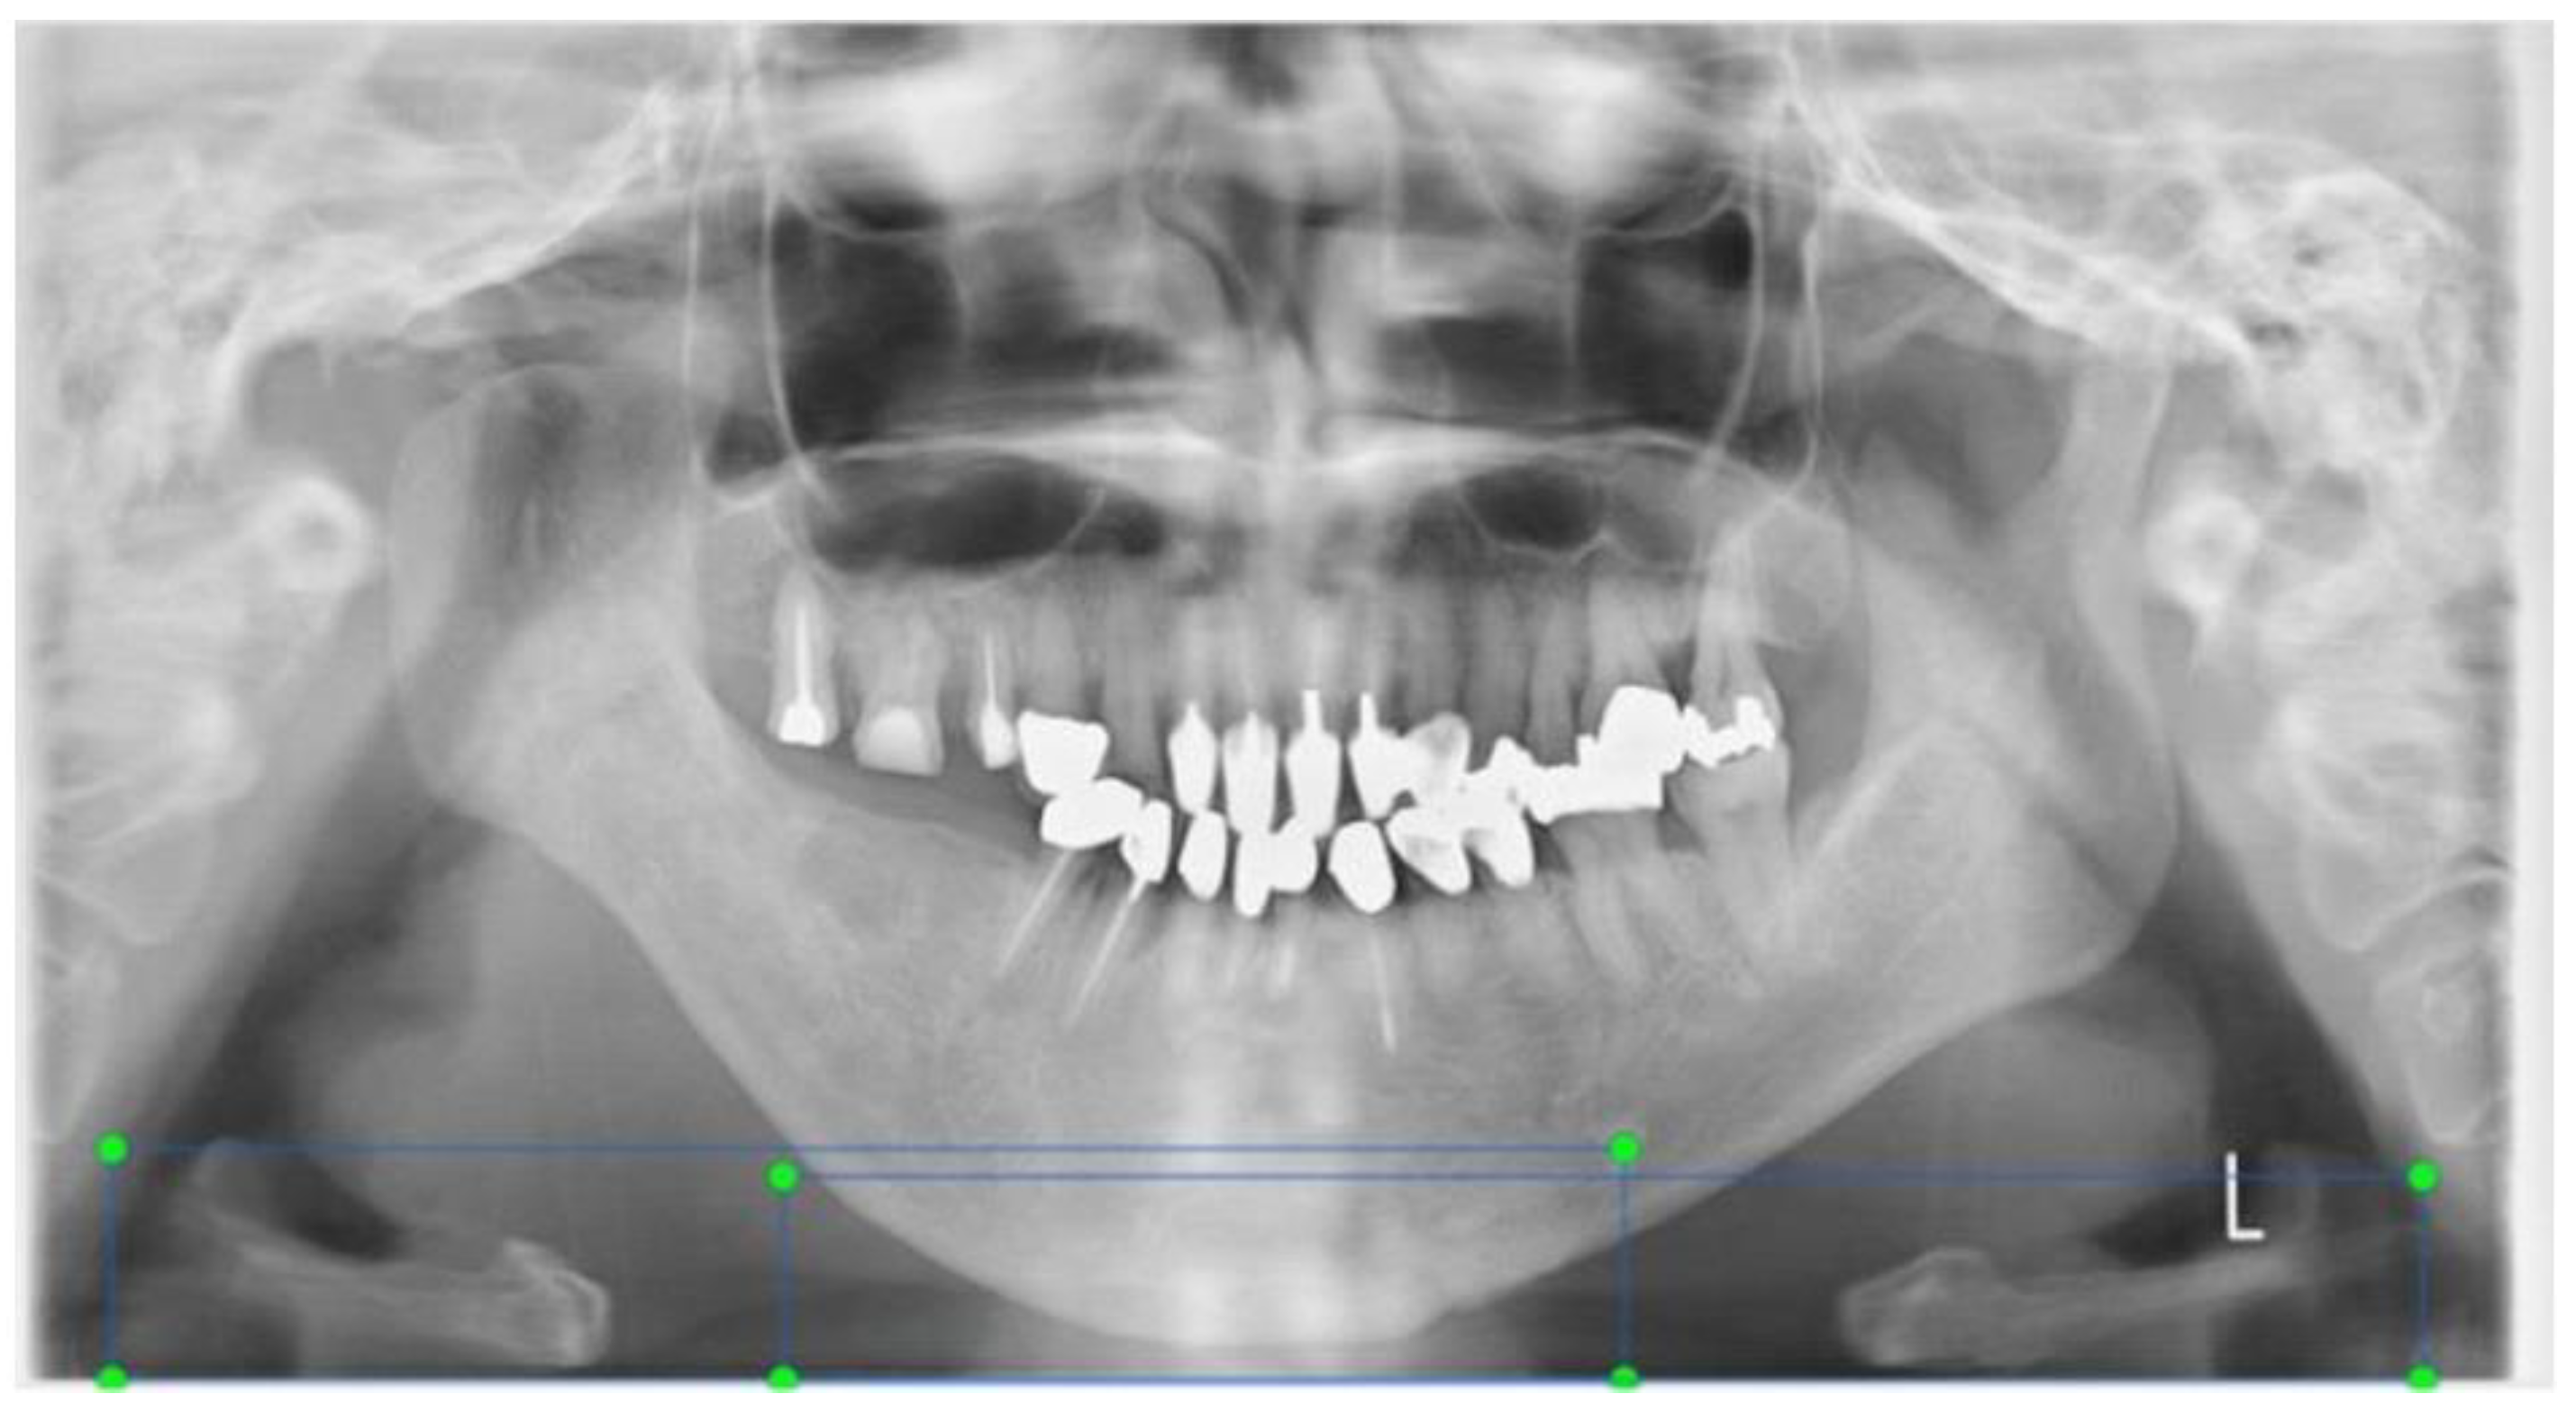

2.1. Acquisition of Panoramic X-ray Images

- The bilateral mandible line: A simulated line connecting the right and left sides of the angles of the mandible.

- The mandibular border line: The line that moved the bilateral mandibular line parallel to the lowest point of the lower border of the mandible.

Annotations